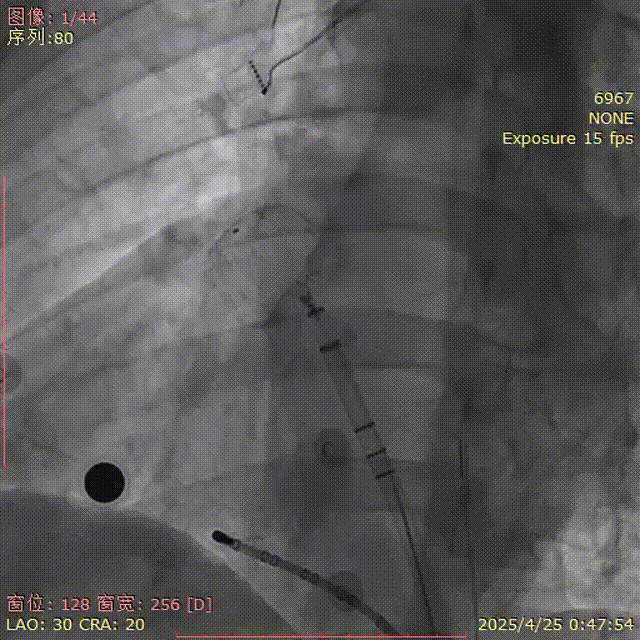

肩位造影

LAO 30° CRA 20°

肝位造影

LAO 30° CAU 20°

牵拉后再造影

肝位及纯足位下缘轻微露肩(少于封堵器尺寸1/3),肩位下无明显露肩,评估符合PASS原则

CAU 30°